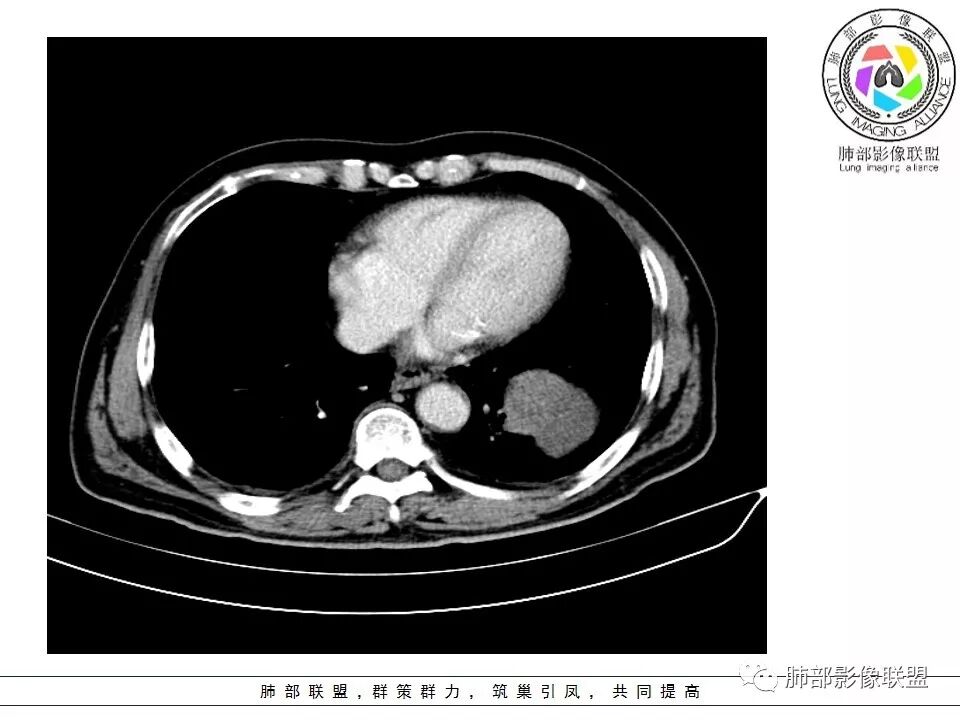

老年男性咳嗽,左下近肺门团块影,不规则强化伴坏死,左下肺静脉、支气管旁淋巴结转移受压、并侵犯左下支气管,考虑鳞癌,鉴别小细胞。

男,70岁,左下肺肿块影,分叶,增强有较大范围坏死,左肺门肿块影,跨叶,包绕支气管与肺门血管,致其狭窄考虑为淋巴结肿大,综合考虑为恶性肿块,鳞癌并左肺门淋巴结转移

肺门淋巴结有肿大,支气管内有肿物,这么大病灶没有坏死,我考虑神经内分泌癌或者小细胞肺癌。鳞癌不符合没看到明显阻塞

老年男性,咳嗽主诉,胸部ct左侧肺门新生物,支气管阻塞,不均匀强化,伴淋巴结肿大,考虑鳞癌,鉴别小细胞肺癌。

老年男性,左下占位,类圆丶浅分叶,无毛刺及胸膜凹陷征,各支气管狭窄,增强不均匀强化,左肺门淋巴结肿大考虑恶性,小>鳞

患者老年男性,以咳嗽就诊,胸CT:左肺下叶占位,病灶呈膨胀性生长,左肺下叶气管明显狭窄,病灶边缘光滑,并可见分叶,增强可见病灶内低密度区,病灶边缘强化。考虑恶性,鳞?肉瘤?

左下肺团块影,不规则强化伴坏死,左下肺静脉、支气管旁淋巴结转移,并侵犯左下支气管,考虑恶性病变,小细胞?

左肺主支气管下肿块,病变包绕并向腔内生长,无阻塞性肺炎,内部可见穿行血管,增强后可见实性明显强化,纵隔淋巴结肿大,老年男性,考虑:神经内分泌癌(类癌、小细胞癌),淋巴瘤,鳞癌

病史:男,70岁,咳嗽;影像:肺门淋巴结,淋巴结内血管毛糙不规则,静脉期,转移大,左心房左下静脉下支是否有累及。主体病灶,呈扇形,沼泽样,指状突起。肺气肿并不明显,左侧少许,左上叶支气管狭窄,肺窗点状凸起,纵膈窗并没有,考虑淋巴结压迫所致。老王曾经说过,小细胞来不及跑得快,胸膜目前没有积液是否是这个原因?诊断:恶性,小细胞肺癌;鉴别:鳞癌,不太像,其他神经类分泌恶性肿瘤;处置:经皮穿刺或EBUS。

左下肺占位性病变,伴肺门淋巴结肿大,强化示不均匀明显强化,可见边界不清坏死区,考虑恶性肿瘤!病灶缺乏分叶及毛刺,整体圆顿,病理倾向大细胞!

左下肺肿块,不均匀强化,其内可见坏死或粘液,更多考虑坏死,左下肺支气管堵塞,左肺门多发肿大淋巴结,左下肺癌,鳞癌可能性大鉴别于小细胞癌

病灶从外向里长,气管狭窄,血管受侵犯,肺门纵膈淋巴结肿大,考虑恶性,首先考虑小细胞癌

左下肺占位伴肺门淋巴结肿大,病灶呈膨胀性生长,左肺下叶气管明显狭窄推移,病灶边缘光滑,并可见分叶,增强可见坏死,病灶边缘强化,阻塞性肺炎不明显,恶性没问题,考虑低分化腺癌,鉴别神经内分泌肿瘤,无冰冻感觉,坏死明显,小细胞不支持,排除大细胞与类癌

老年男性,症状轻。左肺下叶类圆形肿块,边界清楚,分叶不明显,其内无空泡征,边缘无毛刺及胸膜牵拉,远端无阻塞性肺炎。左肺门影增大。增强扫描左肺下叶肿块可疑轻度强化(无平扫对比),局部见小尾巴征。左肺门区见不规则形团块,似多个结节融合,肺动脉受压穿行于病灶中,形成冰冻肺门感觉,局部层面似见肺门区团块与左肺下叶肿块相连。综合考虑小细胞肺癌(SCLC)。

左肺下叶肿块,边缘膨隆,分叶略浅,占位效应明显,远端没有明显花花草草,其内部不均匀强化,坏死边界不清,可见受累的强化血管穿行,是否有钙化?没有平扫,不清楚;同侧肺门淋巴结受累,包绕支气管生长,并突入下叶支气管,导致管腔闭塞及狭窄,考虑恶性没问题,肿瘤既有由外向内生长侵犯又有冰山征的感觉,小>类癌>低分化腺>鳞

病灶从外向内生长,气管狭窄,血管受侵犯,肺门纵膈淋巴结肿大,考虑恶性,腺癌。鉴别小细胞肺癌。

左下肺占位,边缘分叶彭隆,远端无明显阻塞性炎性,考虑外朝内生长为主,增强扫描边缘及病灶内均可见强化,血管破坏。考虑恶性,间叶组织来源,肉瘤?

段支气管管壁破坏比较明显了,小细胞可以破坏力这么强吗?

左肺下叶肿块,内部坏死明显,整体从外向内生长,下叶支气管及舌叶支气管被包绕生长,肺门区淋巴结肿大,坏死。远端无明显阻塞及不张,综合来看,恶性肯定,肺癌,整个病灶有分别有支持小细胞、鳞癌,腺癌及肉瘤样癌的地方,但又不典型,以低分化腺癌或肉瘤样癌或混合性癌(腺癌小细胞混合,低化分腺鳞癌混合),神经内分泌癌可能性大,单纯的鳞癌或小细胞癌有可能,但确实不典型了。至于间叶来源的恶性肿瘤,很少这样从向外内生甚至包绕支气管壁生长,再加上相对罕见,可能性小。

腔外浸润为主,腔内无明显堵塞,原发肿块推移支气管为主,边缘光滑,轻微分叶,肺门引流区淋巴结肿大,而纵隔淋巴结无明确受累,综合考虑,癌:低分化腺癌?大细胞癌?肉瘤样癌?间叶组织肿瘤:肺肉瘤,罕见

左肺门乱乱的,有血管受压表现,有支气管腔内占位表现,肺门淋巴结肿大肯定是有的;左肺下叶见一巨大包块,边缘光滑,内侧又一个切迹,考虑是病变受到了小叶间隔阻挡造成的其内部大部分不强化,但有局部一小片强化;壁不均匀环形强化,总体较薄;周围没有阻塞性肺炎,感染性病变应该是不考虑的,因为周围清楚,也没有感染的症状,还是考虑肿瘤性病变;关键是它边缘光滑,内部应该是坏死,但有强化提示坏死不彻底,这么大了,边缘恶性征象不明显,不符合腺癌,鳞癌呢也不太符合,阻塞性肺炎没有,坏死太明显了,这么大,边缘光滑,坏死明显,符合肉瘤和肉瘤样癌,不除外小细胞肺癌

南边:病灶分为两大块,外围囊实性大肿块,支气管关系不密切,内带多发淋巴结,侵犯支气管、肺血管,恶性没问题,按理间叶为主,或不典型的癌,这不是一个中央型的肺癌,是外朝内进展的,奇怪的是边界这么清楚光滑,一般癌肉瘤、肉瘤类多,其次才是癌,远端也没有阻塞,大方向是这样,恶性,间叶来源?或者混合,恶性程度较高,鉴别就是结核,因为结核是妖

1.左肺下叶近肺门区肿块,肿块外围大,内带小,提示外围向中央生长,符合周围型SCLC沿支气管方向生长。

2.病灶边缘光滑,未见明显分叶、毛刺,符合神经内分泌癌、癌肉瘤及间叶来源肿瘤。

3.病灶内密度偏低,穿行血管未见明显异常,轻度不均匀强化,为乏血供病灶。病灶内可疑坏死区,未见空洞;乏血供符合SCLC,但坏死区不符合。

4.病灶区支气管以受压推移为主,管腔不规则,腔内通而不畅,提示病灶粘膜下为主,符合SCLC迁徙蔓延或间叶来源肿瘤。

5.病灶内有血管走行,血管局部受压,但是强化考虑为乏血供,提示病灶内肺动脉并不是供血血管,只是病灶侵袭性强把血管包埋而已,为血管包埋征;血流面光滑,血管包埋符合SCLC。

6.左肺门淋巴结肿大,与病灶局部融合分界不清,呈冰冻肺门;而纵隔内未见肿大淋巴结,冰冻肺门符合SCLC,但是病灶主体那么大,纵隔内没有明显肿大淋巴结,不是很符合SCLC娘小崽大的特点。

7.未见明显阻塞性炎症及阻塞性肺不张,更加提示病灶从外围向中央侵犯,符合SCLC罕见阻塞性肺不张。